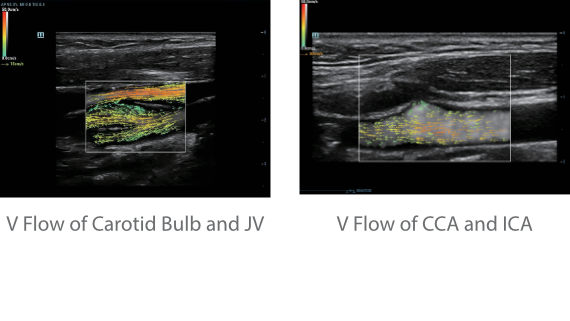

As well as the premium level image quality, Resona 7 also enhances clinical research capabilities with the revolutionary V Flow for vascular hemodynamic evaluation, and the most intelligent plane acquisition from 3D datasets for fetal CNS diagnosis. Combining the most intuitive gesture-based multi-touch operation and all the essential clinical features, Resona 7 is truly leading new waves in ultrasound innovation.